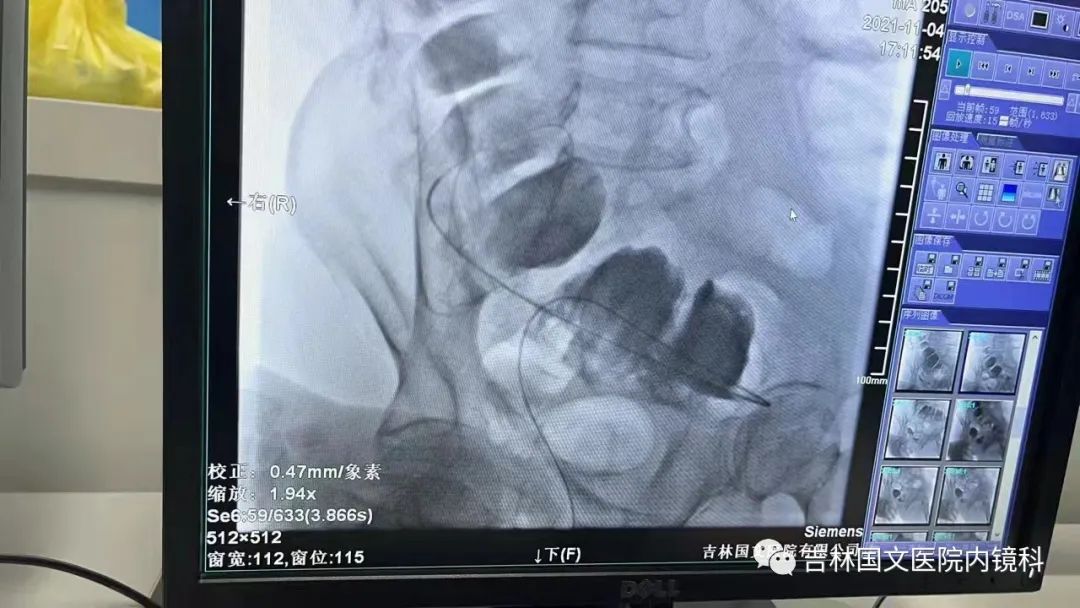

這是一位腸癌的患者,腫物生長在乙狀結(jié)腸,將腸腔堵得只剩一個小孔,糞便自然很難通過,腸梗阻的癥狀使患者十分難受,已多天未排氣排便,患者十分瘦削,開始侯主任未借助任何工具探查一番,結(jié)果就是腸道太迂曲了,實(shí)在無法順利將導(dǎo)絲置入,通過邢主任使用腸鏡在前面引路一直到達(dá)病變部位,這時候侯主任將帶有外套管的導(dǎo)絲從活檢口插入,外套管抵在小孔處,導(dǎo)絲順利進(jìn)入,第一步成功。第二步就是將支架順著導(dǎo)絲送入指定位置,又是一大難關(guān),導(dǎo)絲十分軟,缺乏支撐力,腸道的彎曲十分陡峭,一用力支架抵在腸道低處,患者痛感極強(qiáng),只能另想辦法,嘗試多次后,在兩位主任的豐富經(jīng)驗(yàn)和堅持不懈的努力下,支架順利置入,為患者解除了痛苦。